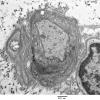

PERIPHERAL NEUROPATHY

3 NORMAL MYELIN & SCHWANN CELLS